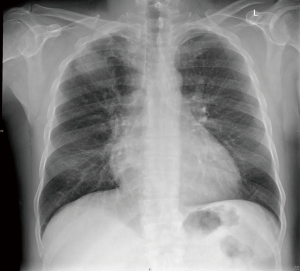

We report a 62-year-old male, presented with shortness of breath and cough. He is diabetic, hypertensive, and is known to suffer from chronic obstructive pulmonary disease (COPD). He is a heavy smoker for more than 40 years. His chest X-ray showed right upper lobe mass (Figure 1).